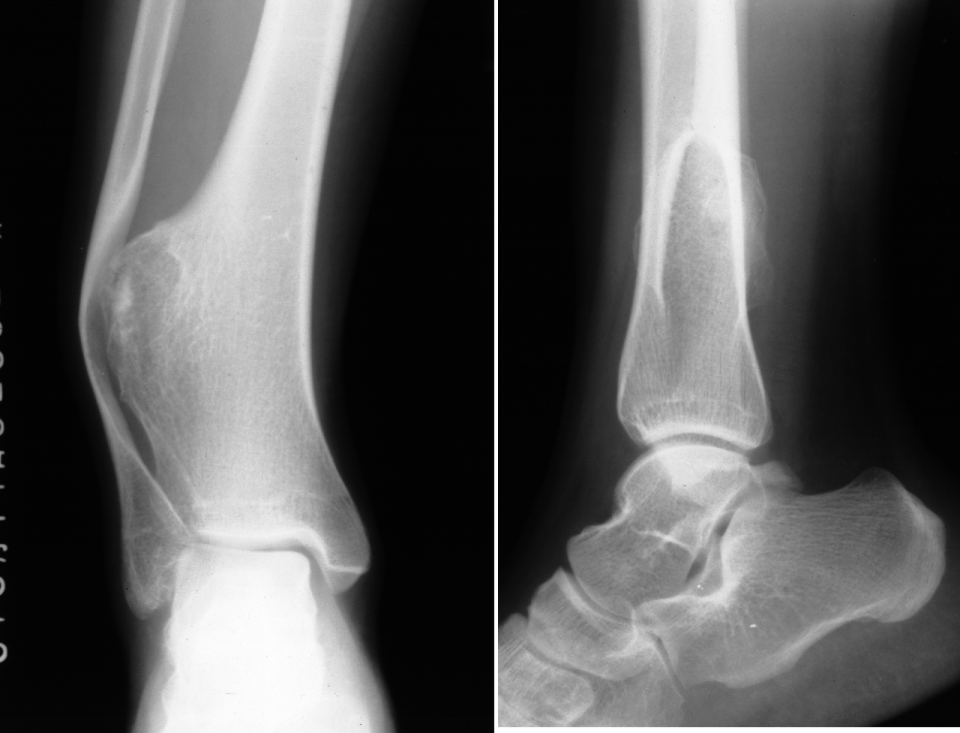

▌膨胀性破坏

膨胀性破坏是地图样破坏的特殊形式,影像学表现为骨质破坏区骨膨胀,周围可见不同程度扩张的骨壳(图 5、图 6、图 7、图 8)。膨胀性破坏是由于肿瘤从骨皮质内面破坏,骨外膜增生形成新生骨造成膨胀的。引起膨胀性破坏见于大多数良性肿瘤和肿瘤样病变如单纯性骨囊肿,动脉瘤样骨囊肿、内生软骨瘤和软骨粘液纤维瘤等,少数也可见于恶性肿瘤如转移瘤、骨髓瘤等。

图 7.膨胀性破坏:内生软骨瘤

图 8.膨胀性破坏:软骨粘液样纤维瘤